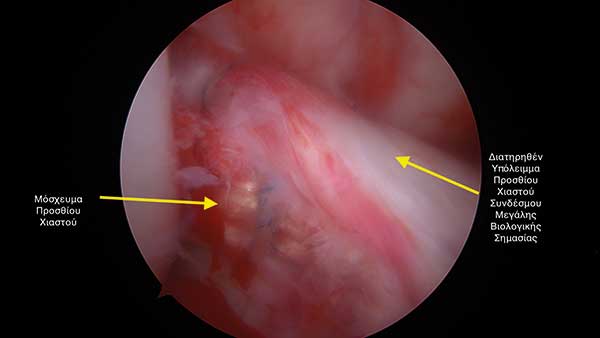

Κατά την επέµβαση αποκατάστασης του προσθίου χιαστού χρησιµοποιούνται συνήθως τενόντια µοσχεύµατα από τον ίδιο τον ασθενή τα οποία υποκαθιστούν τον ρηχθέντα σύνδεσµο. Μάλιστα, ο τελευταίος αφαιρείται πλήρως κατά την επέµβαση της συνδεσµοπλαστικής. Μελέτες έχουν δείξει πως ο «τραυµατισµένος» πρόσθιος χιαστός σύνδεσµος περιέχει σηµαντικά βιολογικά στοιχεία που ονοµάζονται µηχανοϋποδοχείς.

Κατανοώντας τη βιολογική σηµασία του «υπολείµµατος» του προσθίου χιαστού ο κ. Μπουτσιάδης αναπτύσσει µια νέα τεχνική διατήρησης αυτού η οποία δηµοσιεύεται το 2015 (Arthroscopy Techniques).

To υπόλειµµα αυτό διαθέτει κύτταρα και δυναµική ώστε το µόσχευµα που χρησιµοποιείται κατά την επέµβαση να µετατραπεί στο βάθος του χρόνου σε «φυσιολογικό χιαστό».

Προτείνουµε στον ασθενή µια ολοκληρωµένη θεραπεία (Εικόνες 3 & 4):

Πλήρης διατήρηση του υπολείµµατος του προσθίου χιαστού µε σκοπό την πλήρη επαναφορά του γόνατος στη φυσιολογική του κατάσταση.